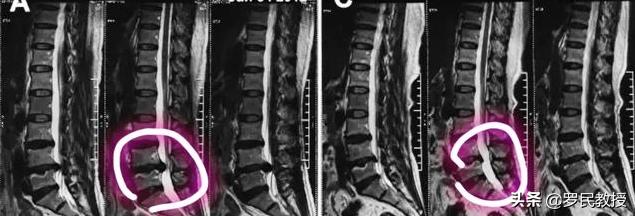

La réponse est oui, mais pas chez tous les patients. En termes de régression de la hernie intervertébrale lombaire, il existe plusieurs types de hernie : le rétrécissement de la hernie (rétraction, résorption), la calcification progressive de la hernie sans modification de la taille de la hernie, l'élargissement de la hernie et le prolapsus de la hernie (rupture de l'anneau fibreux du disque, rupture du ligament longitudinal postérieur).